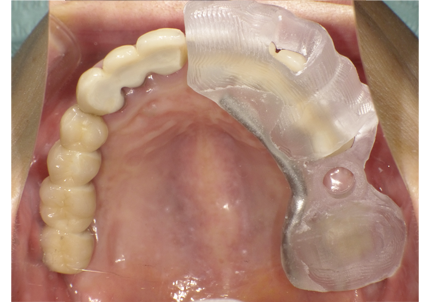

5.仮歯装着歯装着

6.インプラントシリンダーテック作製

7.最終補綴作製(前歯部アバットメント装着)

8.ジルコニアフレーム、アバットメント試適

9.セラミック焼成

10.上顎補綴物装着(2008年12月)

12.上顎補綴物装着(2009年5月)